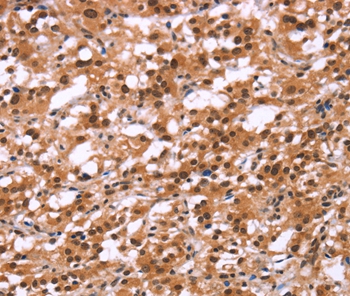

图片:

Immunohistochemical analysis of paraffin-embedded Human thyroid cancer tissue using #37619 at dilution 1/25.

应用详情:Immunohistochemistry: 1:25-1:100